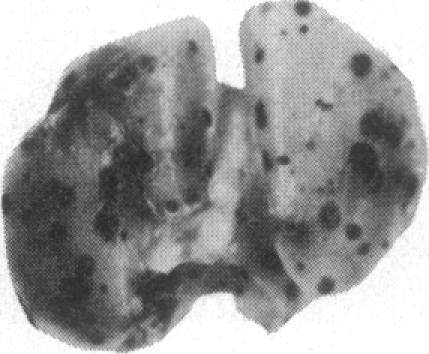

通过苦马豆素处理进行寡糖修饰可抑制B16-F10小鼠黑色素瘤细胞在肺部的定植。

Oligosaccharide modification by swainsonine treatment inhibits pulmonary colonization by B16-F10 murine melanoma cells.

Oligosaccharide moieties of cell-surface glycoconjugates are thought to be involved in recognition events associated with tumor metastasis and invasion. Using swainsonine (SW), an inhibitor of Golgi alpha-mannosidase II that results in the formation of hybrid-type oligosaccharides on N-linked glycoproteins, we have tested the hypothesis that specific glycan structures are required for pulmonary colonization by tumor cells. B16-F10 murine melanoma cells were treated with SW in growth medium and then injected intravenously into syngeneic C57BL/6 mice. This treatment resulted in dramatic inhibition of colonization, but it had no effect on B16-F10 viability or on cellular tumorigenicity after subcutaneous implantation. SW-treated radiolabeled B16-F10 cells were cleared from the lungs at a greater rate than control cells, suggesting that one effect of treatment is to alter tumor cell retention in the target organ. Our results implicate specific glycan structures in pulmonary colonization and offer a potential approach for identification of specific macromolecules involved in tumor cell-organ recognition during metastasis.

摘要

细胞表面糖缀合物的寡糖部分被认为参与了与肿瘤转移和侵袭相关的识别过程。我们使用了苦马豆素(SW),一种高尔基体α-甘露糖苷酶II的抑制剂,它会导致N-连接糖蛋白上形成杂合型寡糖,来检验肿瘤细胞在肺部定植需要特定聚糖结构这一假说。将生长培养基中的B16-F10小鼠黑色素瘤细胞用SW处理,然后静脉注射到同基因的C57BL/6小鼠体内。这种处理导致定植受到显著抑制,但对B16-F10细胞的活力或皮下植入后的细胞致瘤性没有影响。与对照细胞相比,经SW处理的放射性标记B16-F10细胞从肺部清除的速率更快,这表明处理的一个作用是改变肿瘤细胞在靶器官中的滞留情况。我们的结果表明特定聚糖结构与肺部定植有关,并为识别转移过程中参与肿瘤细胞-器官识别的特定大分子提供了一种潜在方法。